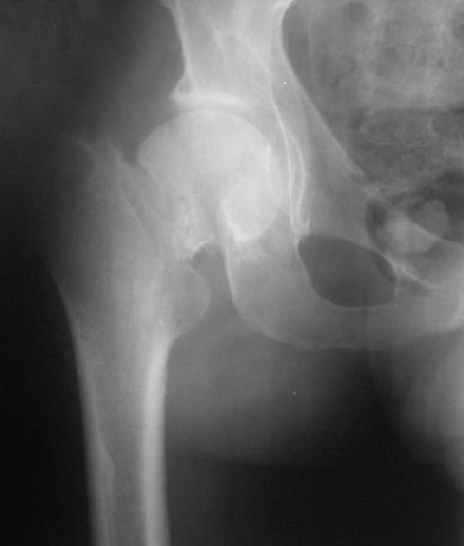

Нелеченный перелом шейки бедра / Neglected femoral neck #

Глубокоуважаемые коллеги, Вчера обратился мужчина 31 г. Травма 2 месяца назад, лечился в одном из городов области. Был не самый тяжелый перелом таза, который проведен консервативно. С ним и связывали невозможность поднять ногу.

Однако на сегодняшнем снимке обнаружился перелом шейки бедра. Больной уже ходит с частичной нагрузкой. Учитывая срок и картину на снимке, что предпринять? У нас предложены варианты 1)не оперировать, 2)закрыто 2 спонгиозных винта, 3)вальгизирующая остеотомия. Эндопротез как-то даже в список включать пока не хочется. Какие есть соображения? Что из перечисленного или что-то другое выбрать и почему? Заранее спасибо.

Dear colleagues, A male 31 years old treated elsewhere after not severe pelvic fracture, was managed non operatively. So the injury looked as a reason of his inability to elevate the leg. However at the recent x-rays the neck fractire was found. The patient already has been walking with partial weight-bearing. Looking at the x-rays and the time since the injury, what is the optimal treatment for now? We discussed 1)leave as is, 2)2 cancellows screws as is, 3)valgus osteotomy. Total hip replacement looks unnecessary yet. What is your opinion? Which option from the listed or something else should be preferred and why? THX in advance.